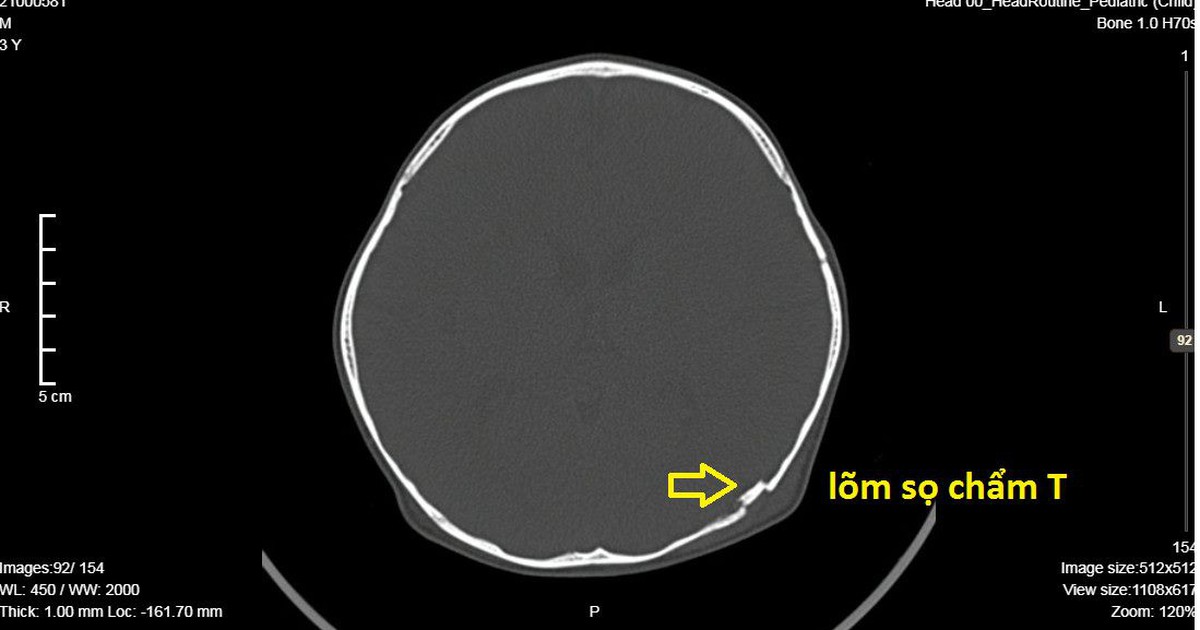

Theo bác sĩ, trẻ em xương yếu, nếu bị chấn thương vùng đầu, sau đó biểu hiện đau đầu, nôn ói, mắt mờ, ngủ nhiều… thì cần nhanh chóng đưa trẻ đến cơ sở y tế thăm khám và kiểm tra để phát hiện tổn thương như lõm sọ não...